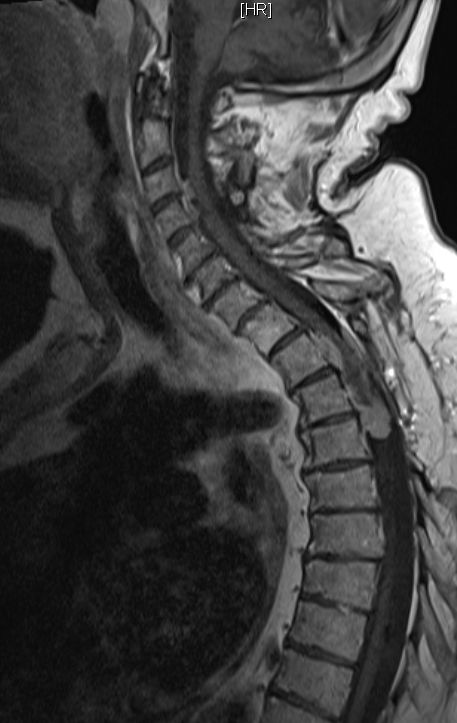

| Rückenmark |

76-jährige Frau mit Rezidiv eines Rückenmarks-Meningeoms. Erstmanifestation vor 17 Jahren. Rezidive von 12, 6 und 3 Jahren jeweils operativ beherrscht. Seit einem Jahr erneut Schmerzen zwischen den Schulterblättern und Druckgefühl im Thoraxbereich. Reduzierter AZ und adipöser EZ. KHK, VHF, Hypertonie, Hypothyreose. Auf Rollator angewiesen. Zunehmende Gangunsicherheit und Kribbeln in den Beinen. Klopfschmerz im Bereich von BWK2-5 stark auslösbar. Die Schmerzen strahlen zeitweise in die Schulterblätter aus. | ![]() | |||||

![]() |

![]() | ||||||